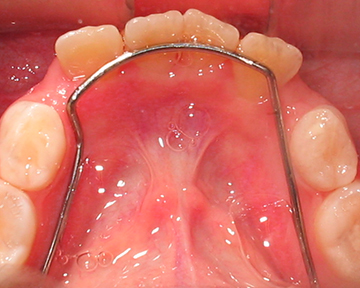

Esto se puede corregir a través de procedimientos capaces de eliminar o reducir su severidad impidiendo que la mala mordida se instale. El objetivo es orientar la salida de los dientes permanentes, para que salgan en los espacios que deben salir.

La idea es que a través de la instalación de aparatos sencillos y fijos (no removibles) el diente permanente realice su erupción de una forma adecuada.